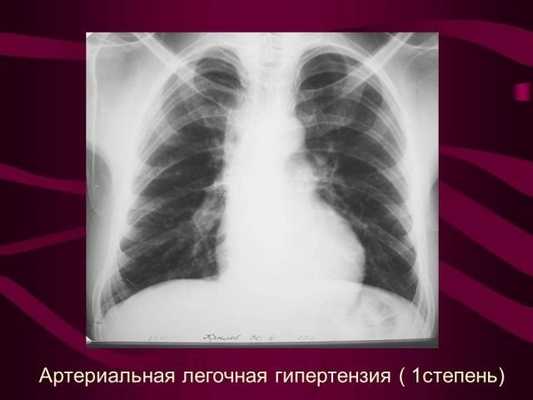

Рентгенография органов грудной клетки позволяет достаточно надежно исключить связанные с ЛГ среднетяжелые и тяжелые заболевания легких и легочную венозную гипертензию, обусловленную патологией левых отделов сердца. При этом нормальная рентгенограмма органов грудной клетки не исключает легкую посткапиллярную легочную гипертензию на фоне заболеваний левых отделов сердца.

У больных с ЛГ в момент постановки диагноза имеются изменения на рентгенограмме органов грудной клетки:

− увеличение правых предсердия и желудочка

- Рентген органов грудной полости. Позволяет, в большинстве случаев, выявить патологические процессы. Наиболее частыми признаками являются расширение диаметра правой ветви легочной артерии и увеличение ее конуса.